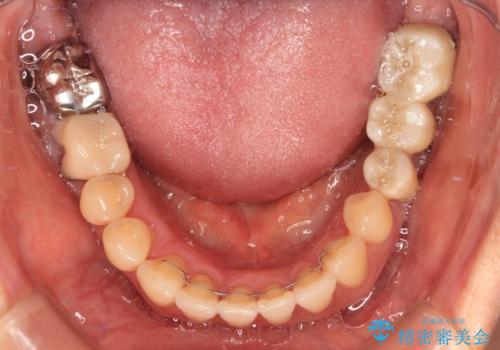

- 飛び出した上顎前歯と正中のズレを気にして来院された患者様です。

上顎正中が右側にずれていたので、むし歯が酷く抜歯が必要な左側臼歯を抜歯して正中を改善することとしました。

左下には新しいセラミックのブリッジが装着されていたため、ブリッジを壊さずに改善できるところまで咬み合わせを改善していくこととしました。

右上小臼歯は銀歯が装着されており、ワイヤー矯正の装置が装着できないため、事前に仮歯に変えてから矯正治療を行い、その後オールセラミッククラウンにて補綴治療を行いました。